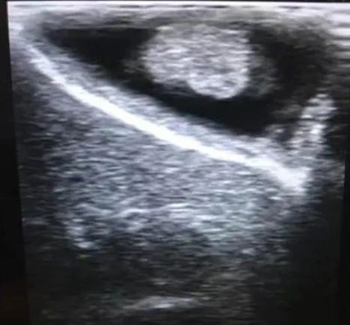

直径超过1cm的息肉存在胆囊癌的可能,是需要手术治疗的。如果保胆取的息肉已经癌变,取的时候存在导致肿瘤腹腔内种植的风险。

超声显示的单发息肉,术后病理提示存在癌变